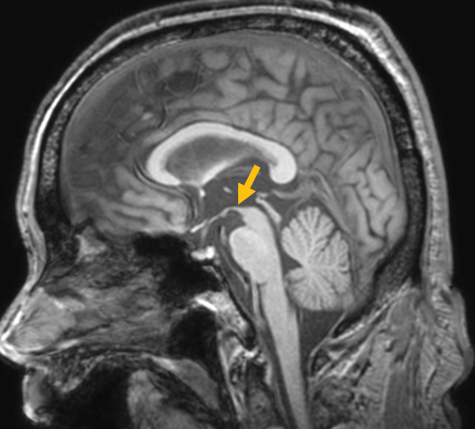

다계통 위축이란 뇌의 다양한 계통에서 위축이 발생하는 것을 의미합니다. 파킨슨 증상이 있으면서 질병 초기에 소변 장애나 기립성 저혈압으로 인한 어지러움이 두드러지게 나타나는 경우, 보행 시 비틀거림이나 구음 장애와 같은 소뇌 위축에 따른 운동 실조 증상이 나타나는 경우, 꿈에서 하는 행동을 수면 중에 보이는 렘수면 행동 장애가 동반되는 경우 다계통 위축을 의심합니다. 다계통 위축은 파킨슨병과 달리 안정 시 떨림이 잘 보이지 않고, 증상이 대칭적인 경우가 많으며, 진행이 빠르며, 레보도파와 같은 항파킨슨 약제에 잘 반응하지 않습니다. 다계통 위축은 뇌 자기공명영상(MRI)에서 교뇌에 십자 모양의 고음영이 나타날 수 있는데, 이를 십자무늬 빵(hot cross bun) 징후라고 합니다. 또한 초기에서는 뇌 자기공명영상(MRI)이 정상으로 보이더라도 뇌포도당 양전자 단층촬영(PET)에서는 소뇌 또는 기저핵의 대사 기능이 저하된 상태가 관찰될 수 있습니다. 이러한 영상 소견은 특징적인 임상 증상과 함께 진단에 참고할 수 있습니다.

[다계통위축 환자의 뇌자기공명영상에서 확인되는 십자무늬빵 징후]